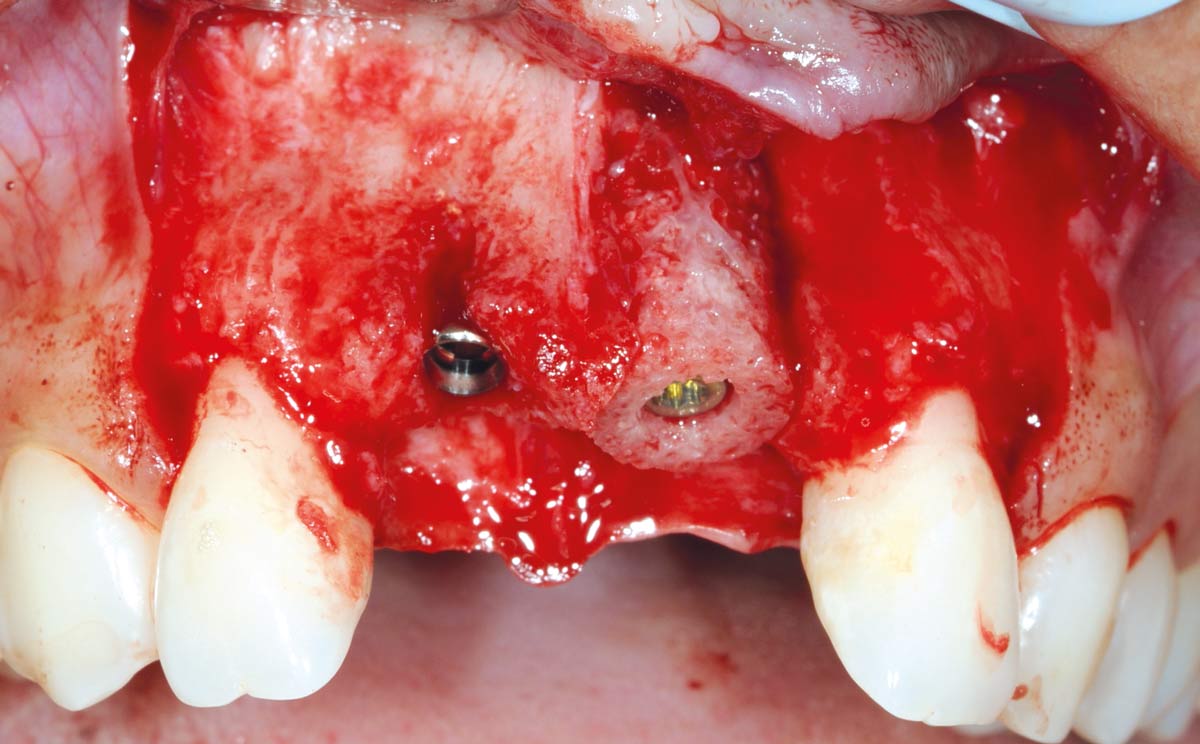

3/26 - Big bone defect visible after opening the flapBone augmentation in aesthetic zone with maxgraft® bonering - Dr. A. Patel